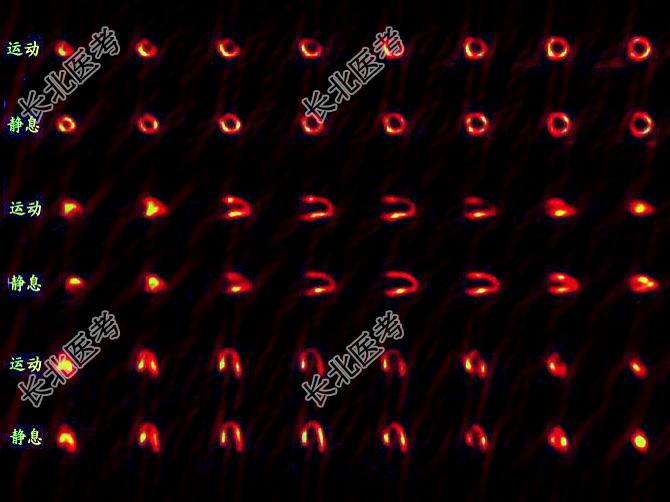

- 多项选择题一患者的心肌灌注显像对比如图,正确的诊断是 ( )

A、左心室前壁可逆性缺血

B、术后再狭窄

C、PTCA疗效显著

D、PTCA无明显疗效